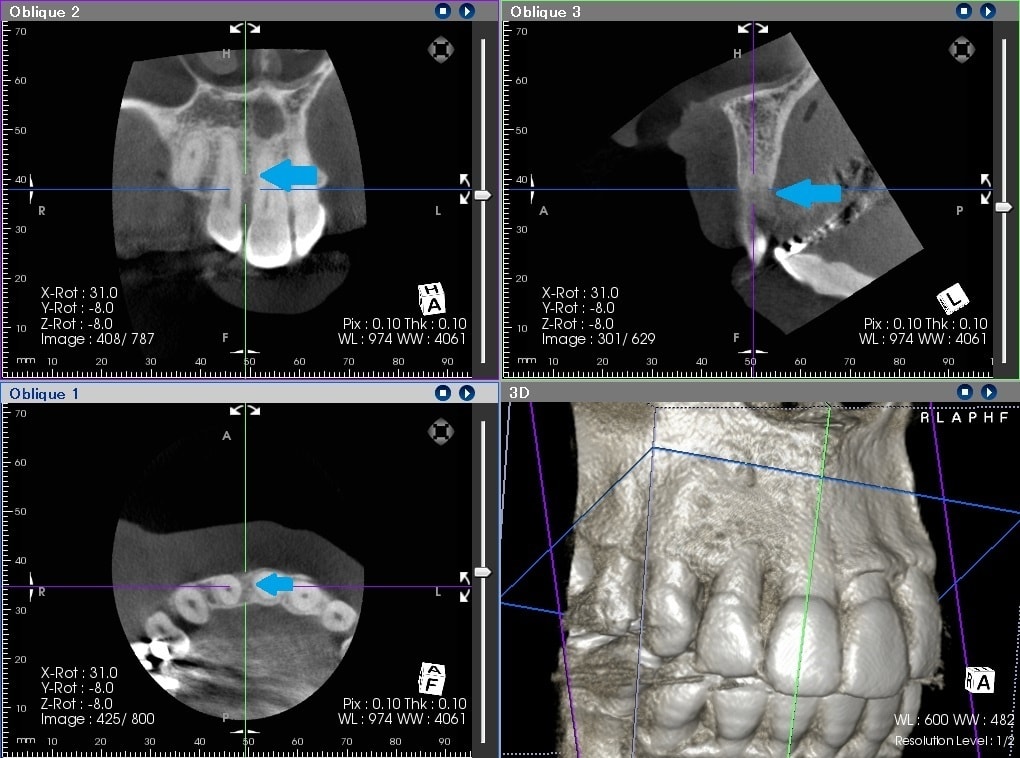

治療前は、赤の矢印で示すように歯の周りに黒いところがあることが分かるかと思います。簡単に言うと、骨が溶けた状態になります。

通常、歯周ポケットと呼ばれる歯と歯茎の間の溝は3㎜程度なのですが、10㎜を超える歯周ポケットがありました。CTは、手術前に骨の欠損形態を的確に把握できるため、歯周病の治療にも非常に有用です。

歯周病の基本的な治療を行い、その後に、歯周組織再生療法という失われた歯の周りの組織を再生させる手術を行って約2年のレントゲンになります。

青の矢印で示すように、治療前黒かった部分が、白くなってきていることが分かるかと思います。失われた歯周組織の再生が促されていることが推測されます。CTにおいても歯の周囲の失われた骨が再生してきていることが、分かるかと思います。